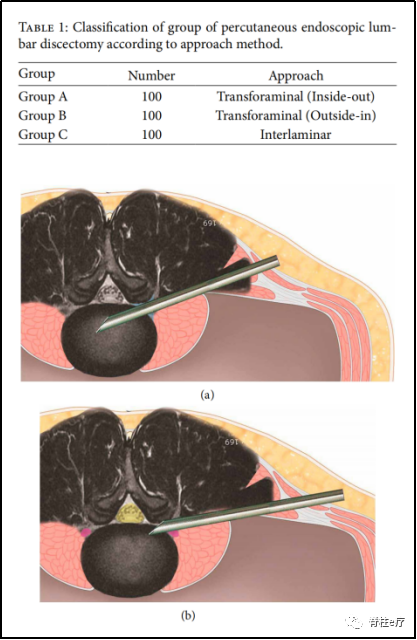

4.手术入路选择

PELD的常见手术入路分为后外侧椎间孔入路和后侧椎板间入路。两种入路在麻醉方式、透视次数、操作难度、手术时间等方面各有所长,选择上主要取决于患者解剖结构和突出位置的不同。但只要术中操作得当,减压彻底即可达到相同的疗效。

图示:两种椎间孔入路(inside-out)、(outside-in)

图示:椎板间入路

有学者[13]报道了300例术后PELD患者,其中两种椎间孔入路(inside-out、outside-in)和椎板间入路各100例,其中出现术后复发病例分别为11% (11/100)、10% (10/100)、7% (7/100),研究表明手术入路与术后复发并无密切相关性。

目前,众多学者同样认为,PELD常见的两种入路与术后复发率的影响并没有显著相关性[14]。